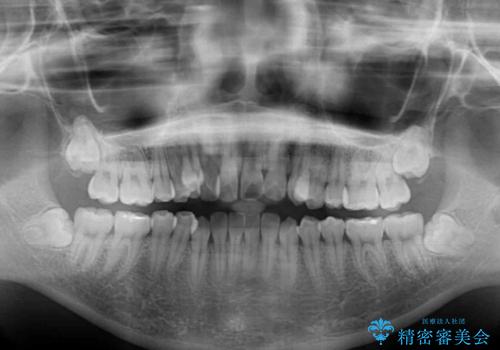

上下の前歯が非接触であり、叢生や八重歯が顕著であったため、上顎左右第一小臼歯2本を抜歯して排列することとしました。

抜歯により移動量が多くなるため、ワイヤーや補助装置を活用し、その後インビザラインによる矯正治療を行うこととしました。

元々奥歯に負担のかかる咬み合わせですり減っていたため、仕上がった歯並びでも奥歯が咬んでいないように見えましたが、実際にはしっかりと咬合しており、患者様本人も咬んだ感触に違和感はないとのことでした。